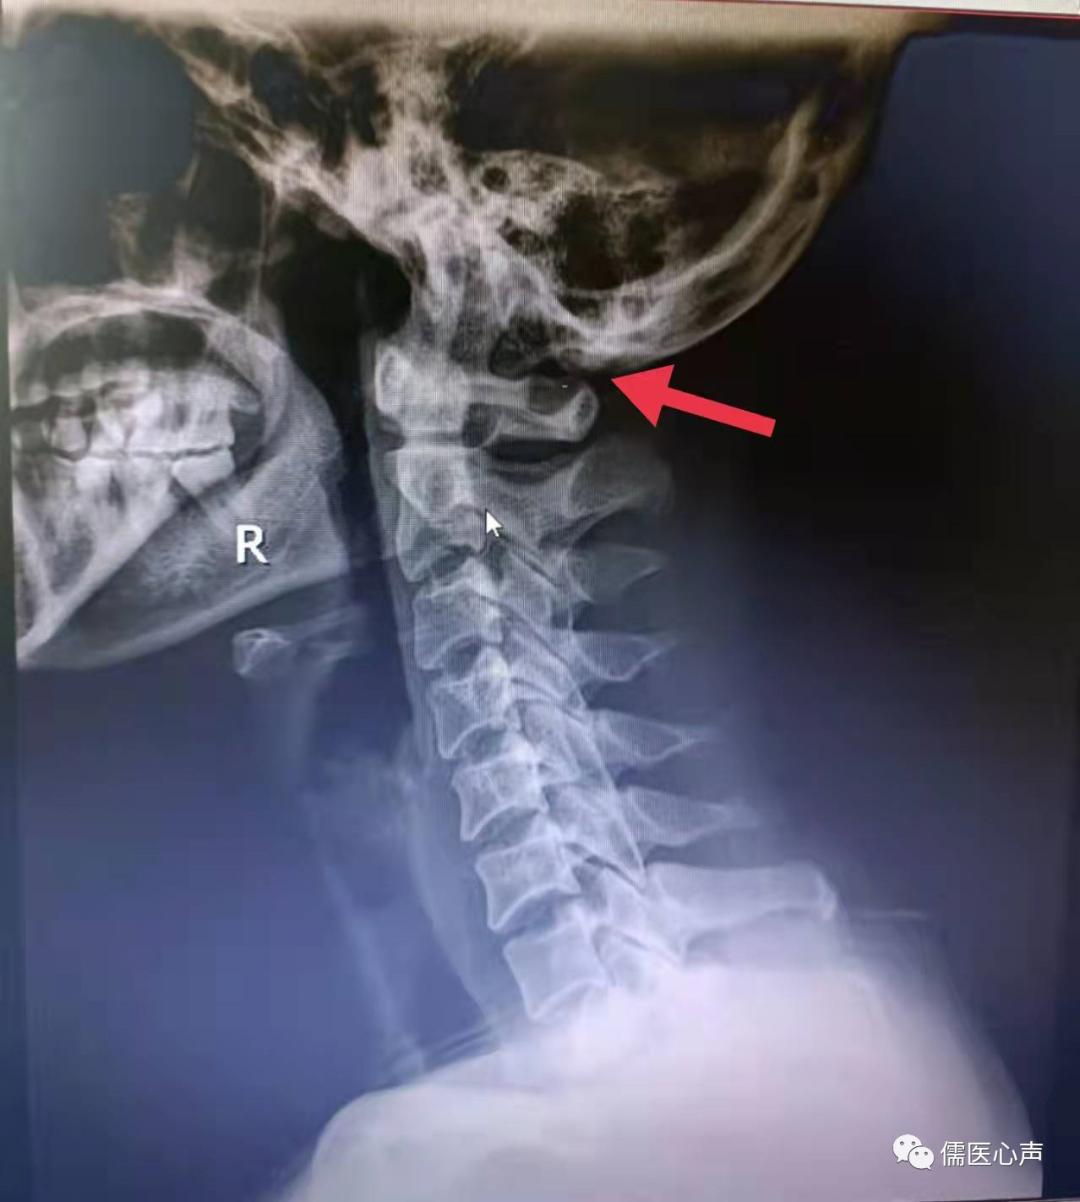

王大姐到底是哪里出了问题呢?头颅、耳内经过多次检查,已排除明显的器质性病变,最大的嫌疑便是颈椎。一张颈椎张口位的x片,让王大姐的病因现出端倪。 寰枕筋膜挛缩综合征 ------这是笔者给王大姐下出的诊断。什么是寰枕筋膜挛缩综合征呢?先来看看寰枕部的局部解剖。

寰枕间隙已严重变窄,环椎后弓与枕骨几乎吻合到了一起。

在正常情况下,枕骨大空的后侧边缘和环椎之间有一个间隙,称之为寰枕间隙,椎动脉在寰椎椎动脉沟里是很宽松的。当寰枕筋膜变性挛缩时,这个间隙就变窄了,椎动脉就会受到挤压,影响大脑供血而引起顽固性头晕,视物模糊等症状,椎动脉受到压迫,局部狭窄,循行的血液就会产生涡流,而出现脑鸣;卡压牵拉刺激到枕大、枕小神经,就会引起顽固性的枕后疼痛。